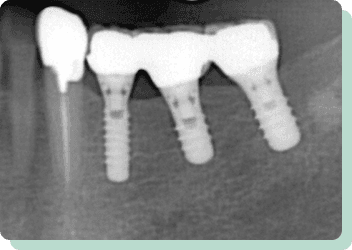

向かって右奥は3本の歯が失われています。入れ歯にすると、バネをかける歯に負担がかかり予後に不安があるだけでなく、満足な咀嚼も期待できません。インプラントを応用することにより、左右でしっかり噛めるようになりました。また、条件が許せば2本のインプラントで対応することも可能です。向かって左側は、見た目の改善を目的にセラミック4本で対応しています。

リスク:疼痛・咬合時痛・冷水痛・出血・インプラント手術による歯ぐきなどの損傷・インプラント周囲炎など

費用:インプラント治療(計3本):1,320,000円

セラミック治療(計4本):350,000円